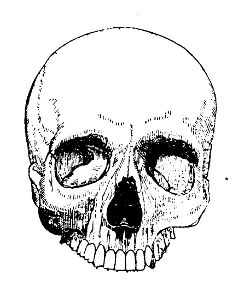

globules are here shown upon a scale of 1/4000 part of an inch, linear,

globules are here shown upon a scale of 1/4000 part of an inch, linear,